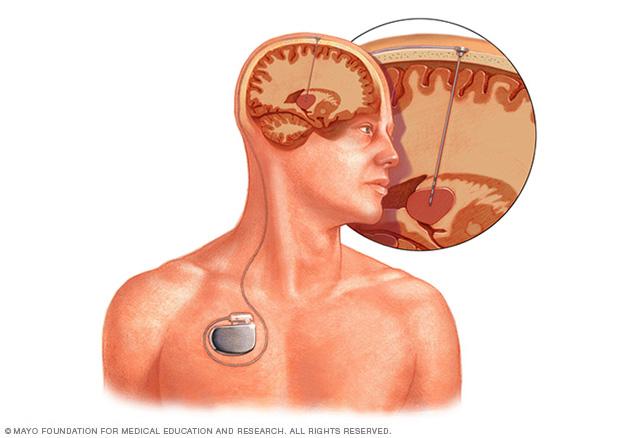

Deep brain stimulation involves placing an electrode deep within the brain. The amount of stimulation delivered by the electrode is controlled by a pacemaker-like device placed under the skin in the chest. A wire that travels under the skin connects the device to the electrode.

• Deep brain stimulation. Surgeons place thin wires called electrodes in certain areas of the brain to produce electrical impulses. The impulses help the body manage the brain activity that causes seizures. The electrodes attach to a pacemakerlike device placed under the skin of the chest. The device manages how much stimulation happens.